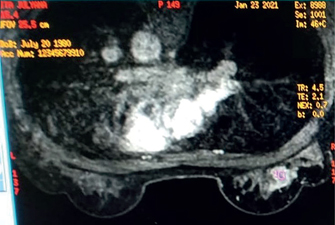

X-ray-based conventional mammography is a routine approach worldwide for breast screening (Figure 1). Several variations of x-ray-based imaging (XBI) technique is available, for example, digital breast tomosynthesis (DBT), and contrast-enhanced digital mammography (CESM), each with its own advantages and disadvantages (1, 3, 6).

Fig 1

Figure 1. Breast cancer mammography imaging: Left, craniocaudal view. Right, mediolateral oblique view. Image was provided by Division of Oncology, Department of Surgery, Faculty of Medicine, Universitas Sumatera Utara.